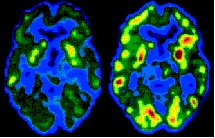

Pero la ciencia de la clonación es ciencia vieja. El campo de la ciencia que hoy promete la revolución más importante es el de la neurobiología, el estudio de los procesos mentales, de la conciencia, de la memoria, de las ideas y los sueños.

Pese a que la reciente década cerebro no cumplió con sus promesas de entender la mente humana, la neurociencia ha quedado en un estado sumamente prolífero, no en cuanto a ideas, sino en cuanto a datos y tecnologías.